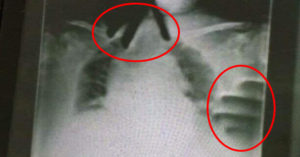

Protected: 自爆初夜献给精选帅哥 校花级女星「开封」结局大翻车 1 分鐘閱讀 There is no excerpt because this is a protected post. February 25, 2023 選擇語言: 还原 简体 繁體 編輯:地方少女 快樂邊緣人(¬‿¬) 星闻, 世界 TEEPR原創 採訪報導 綜合報導 編譯 特稿 This content is password-protected. To view it, please enter the password below. Password: 參考資料:香港01 (往下還有更多精彩文章!) TEEPR 亮新聞著作權聲明:非法抄襲TEEPR 亮新聞網站請注意,本站所有內容皆由自家TEEPR 亮新聞 編輯撰寫,並非如非法內容農場複製貼上。本網站之文字敘述、圖片、影像視聽及其他資訊等,非經授權,不得轉載。如侵權將立刻請臉書封鎖專頁。微改標題、圖片、前段,仍然抓得到! 分類:星闻, 世界 延伸閱讀 世界 在家看电视突传敲门声!开门惊见后院降下「13人热气球」 屋主傻眼:这啥情况 世界 景区吊桥突然断裂!29人瞬间滑落 「5人惨死」现场影片曝光 世界 表演一半护栏倒塌!「老虎冲进观众席」全场吓疯 马戏团团长回应了 世界 恐无限期休园!30多岁人妻被丢进「动物园焚化炉」 分享給好友! 分享至即時通 加入粉絲團! 留言按此 分享! 加入好友 追蹤我們的IG! 上一篇 阿嬤住院突喘不過氣 X光驚現「無骨雙手掐脖」!主治醫出面證實了 下一篇 上課玩Switch被沒收 122公斤學生「飛身衝撞」再重擊21拳!女師倒地不起畫面曝 廣告 廣告